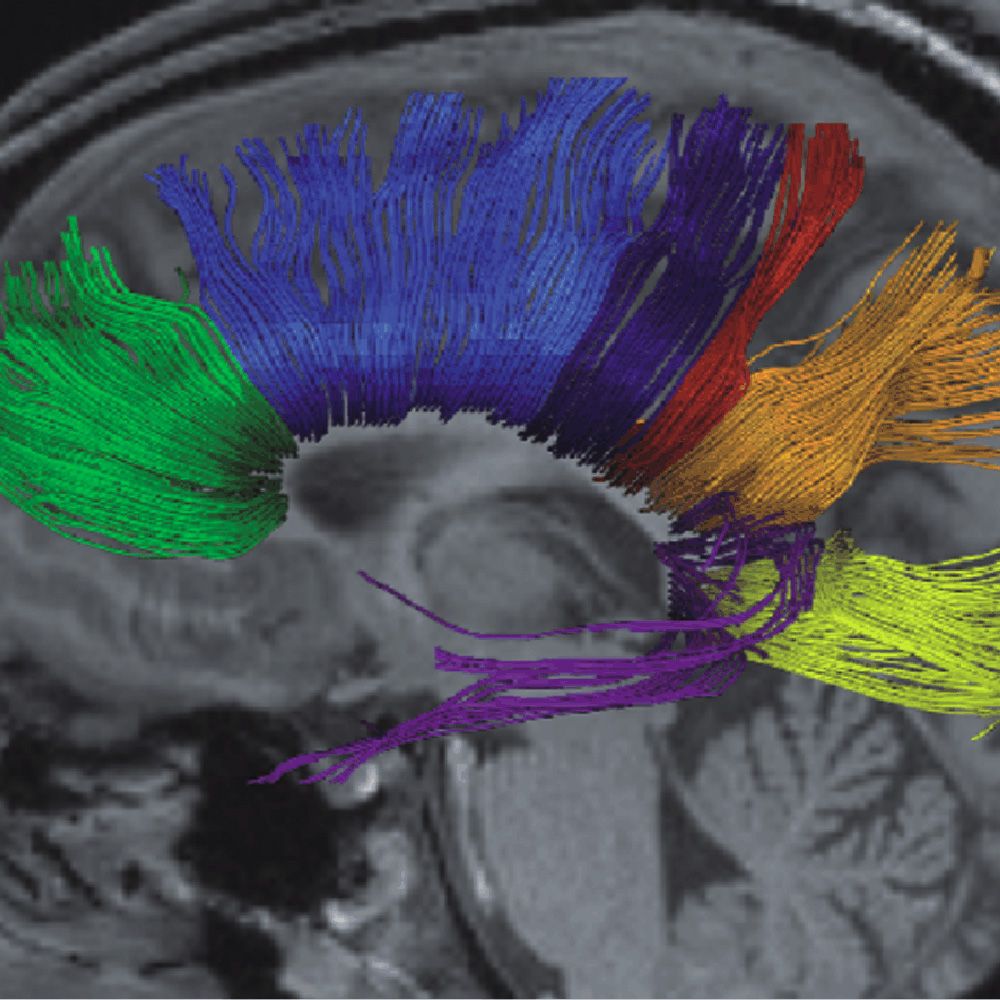

Blick in das Innere des Gehirns: Schädigungen Gehirns können mit Hilfe der MRT genau und für den Patienten risikolos diagnostiziert werden (© MPI für biophysikalische Chemie) -

Faserbahnen im menschlichen Gehirn (© MPI für biophysikalische Chemie)